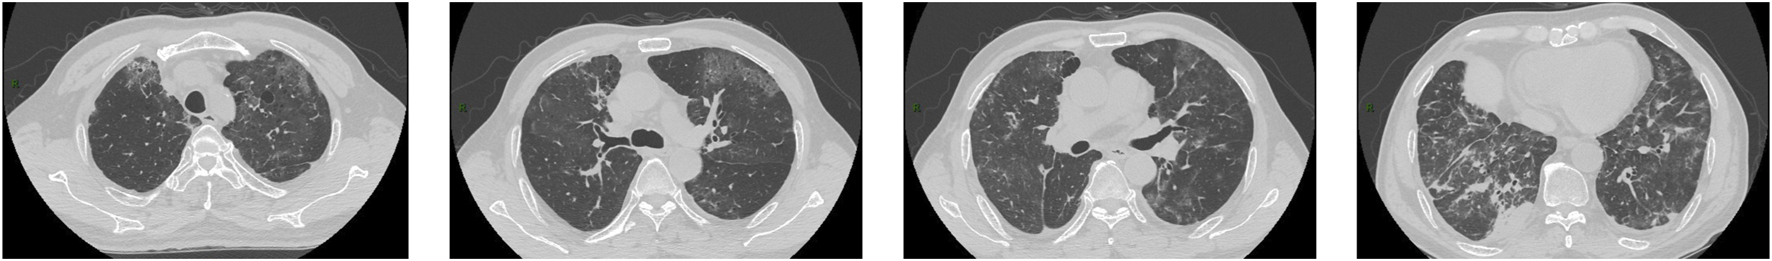

FIGURE 1

CT images obtained on 5 May 2022. The images showed diffuse ground-glass opacities with numerous cystic lesions in both lungs and patchy consolidations in the right lower lung.

Throughout treatment, the patient encountered grade 2 neutropenia according to the National Cancer Institute Common Toxicity Criteria for Adverse Events (NCI-CTCAE, version 5.0). On 3 May 2022, the patient was hospitalized due to a fever of 38.6°C. With an Eastern Cooperative Oncology Group (ECOG) performance status of 1, the patient maintained hemodynamic stability. Oxygen saturation levels were measured at 97% without the need for supplemental oxygen. Auscultation revealed coarse breath sounds bilaterally, accompanied by a few dry rales. Subsequent routine blood tests conducted on the same day disclosed a decline in lymphocyte count (absolute lymphocyte value of 0.54×109/L, reference range 1.1–3.2×109/L) and an elevation in C-reactive protein (CRP) levels (CRP 218.58 mg/L, reference range 0–3.0 mg/L). Following an assessment indicating community-acquired pneumonia, we initiated the intravenous infusion of levofloxacin (0.4 g/24 h). However, 48 h post-admission, the patient developed severe dyspnea, leading to a decrease in oxygen saturation to 90% (without supplemental oxygen), necessitating the use of 40% oxygen to maintain saturation above the established normal threshold (>95%). On 5 May 2022, a computed tomography (CT) scan revealed widespread ground-glass opacities with numerous cystic lesions bilaterally, alongside localized consolidations in the lower right lung (Figure 1). The patient exhibited persistent fever (37.4°C) after admission. Consequently, pralsetinib was halted, and the therapeutic regimen was modified to incorporate moxifloxacin (0.4 g/24 h) along with oseltamivir (75 mg twice daily) in an empirical approach. Furthermore, sputum culture and a battery of tests for respiratory pathogens, cytomegalovirus, and herpes simplex virus DNA assays were conducted. Unfortunately, none of these tests provided informative results. Subsequently, bronchoalveolar lavage (BAL) fluid samples were obtained from the lungs via fiberoptic bronchoscopy for NGS. Despite these interventions, the patient’s clinical condition deteriorated, and oxygen saturation remained at 50%. A subsequent CT scan revealed an expanded range of lesions characterized by interlobular septal thickening (Figure 2). Considering the CT findings and the patient’s clinical presentation, pneumocystis pneumonia was highly probable, prompting the administration of trimethoprim/sulfamethoxazole (TMP-SMZ, 160/800 mg, every 12 h), caspofungin (50 mg/24 h), and clindamycin for anti-infective treatment. Subsequent BAL results confirmed our clinical suspicion, demonstrating positivity for P. jirovecii with a sequence number of 61,636. Consequently, the patient’s condition improved, as reflected in enhanced pulmonary auscultation findings, resolution of fever, and improved blood test results. Due to the favorable progression of his condition, the patient expressed a desire for early discharge after receiving treatment with TMP-SMZ (160/800 mg every 8 h), caspofungin (50 mg/24 h), and clindamycin (0.6 g/8 h) for 3 days. Subsequently, the patient was administered TMP-SMZ (every alternate day) for 2 weeks. The severity of PJP in this patient was classified as grade 3 according to CTCAE.